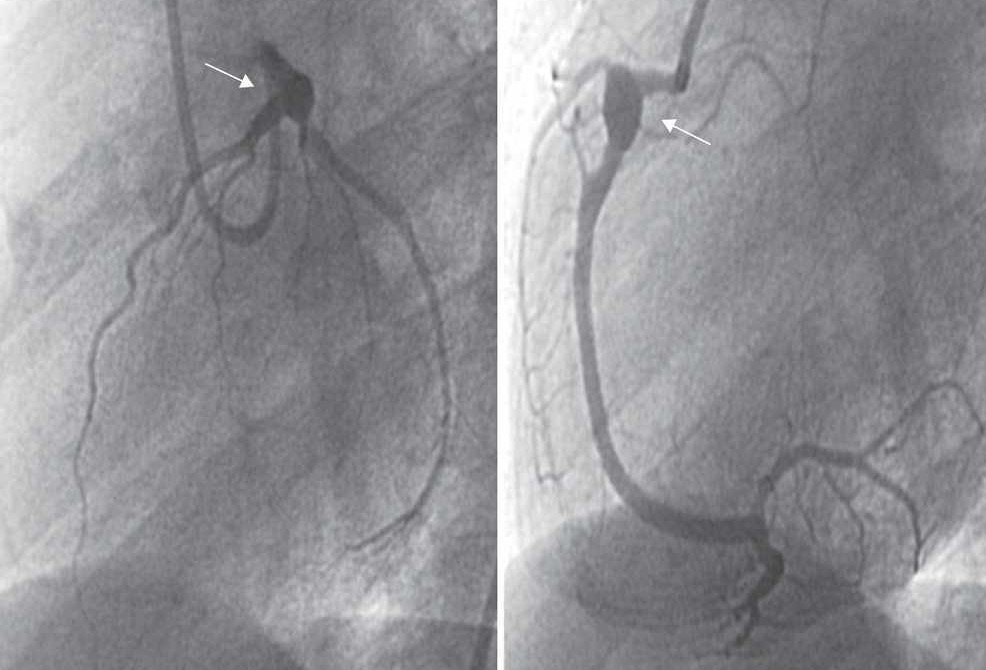

Enfermedad de Kawasaki

Repaso: Enfermedad de Kawasaki

¿Qué es la enfermedad de Kawasaki? La enfermedad de Kawasaki es una entidad aguda, febril, que afecta múltiples órganos en niños. ¿Cuál es la incidencia de la enfermedad de Kawasaki? El…